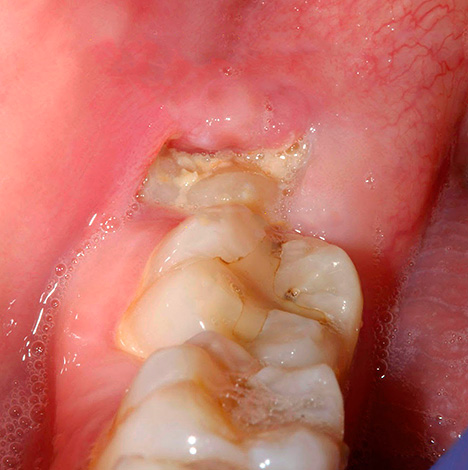

La foto sotto mostra un dente del giudizio semi-rinforzato (cioè è solo parzialmente scoppiato):

La fotografia sotto mostra un esempio di significativa distruzione cariata di un dente del giudizio:

Esempio n. 2: distruzione significativa del dente del giudizio con eruzione incompleta. In altre parole, solo pochi tubercoli del dente del giudizio sono apparsi sopra la gomma, e il resto è sotto la gomma, ma è già stata osservata una grave distruzione cariata.